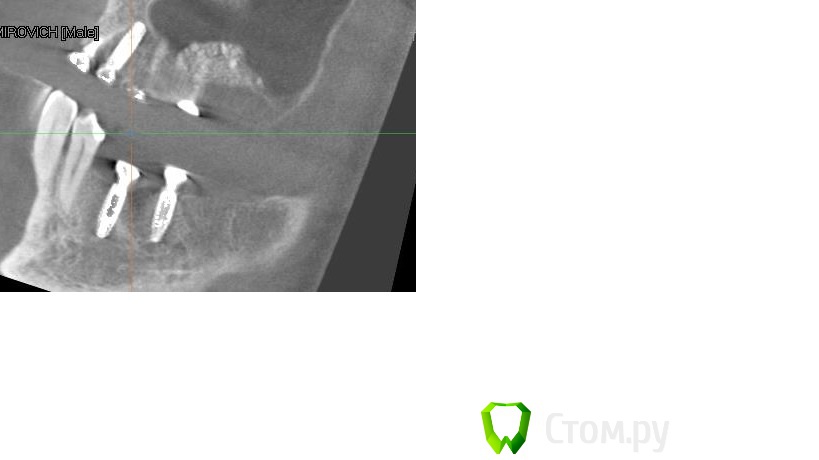

Driv Опубликовано 14 апреля, 2014 Автор Поделиться Опубликовано 14 апреля, 2014 Пойдет? Ссылка на комментарий

Bier Опубликовано 14 апреля, 2014 Поделиться Опубликовано 14 апреля, 2014 да, только надо и остальные 2 окошка тоже. наведите перекрестие на 1 и на другой имплантаты и дайте полную картинку экрана Ссылка на комментарий

Driv Опубликовано 14 апреля, 2014 Автор Поделиться Опубликовано 14 апреля, 2014 Так? Ссылка на комментарий

Bier Опубликовано 15 апреля, 2014 Поделиться Опубликовано 15 апреля, 2014 судя по этим срезам, все хорошо. 1 Ссылка на комментарий

IvanK Опубликовано 15 апреля, 2014 Поделиться Опубликовано 15 апреля, 2014 судя по этим срезам, все хорошо.Согласен Ссылка на комментарий